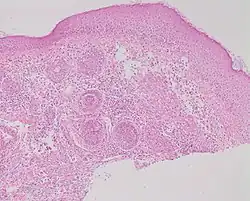

Micrograph showing rosacea as enlarged, dilated capillaries and venules located in the upper dermis, angulated telangiectasias, perivascular and perifollicular lymphocytic infiltration, and superficial dermal edema[20]